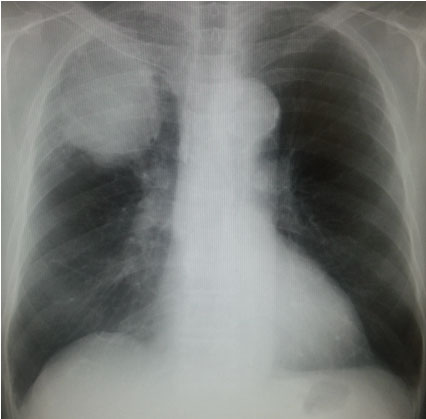

胸部Xp:右上肺に巨大腫瘤陰影